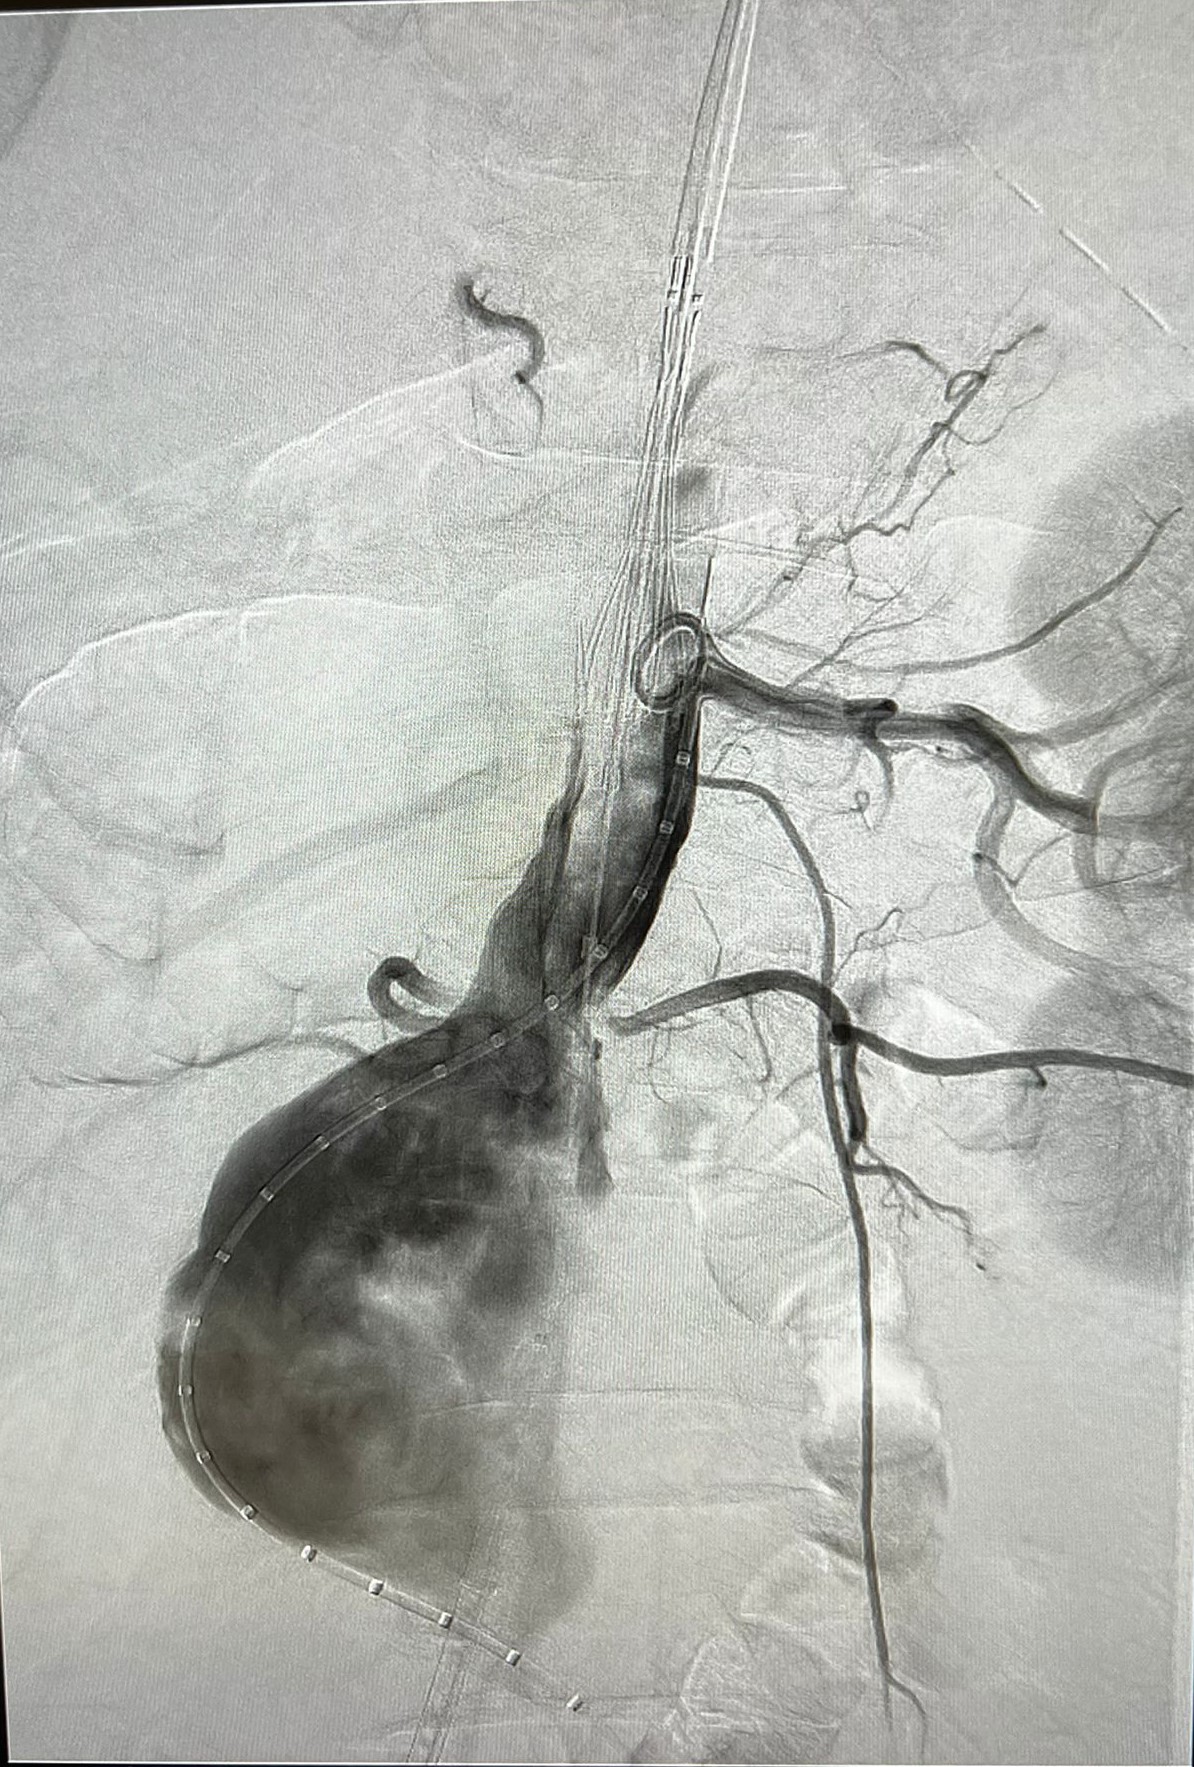

În Clinica de Chirurgie Cardiovasculară a UMF Carol Davila de la Spitalul Clinic de Urgență București (Floreasca) au fost rezolvate săptămâna trecută trei cazuri de anevrism de aortă abdominală infrarenală, dintre care unul rupt.

Soluția adoptată a fost non-chirurgicală: s-a realizat implantarea unor stentgrafturi endoaortice pecutanat (fără incizii chirurgicale) – EVAR, se arată pe pagina de Facebook Chirurgie cardiovasculară Floreasca.

Procedurile au fost realizate de prof. univ. dr. habil. Horațiu Moldovan (foto), Șeful Clinicii de Chirurgie Cardiovasculară, împreună cu colegii chirurgi, cardiologi intervenționali și anesteziști: